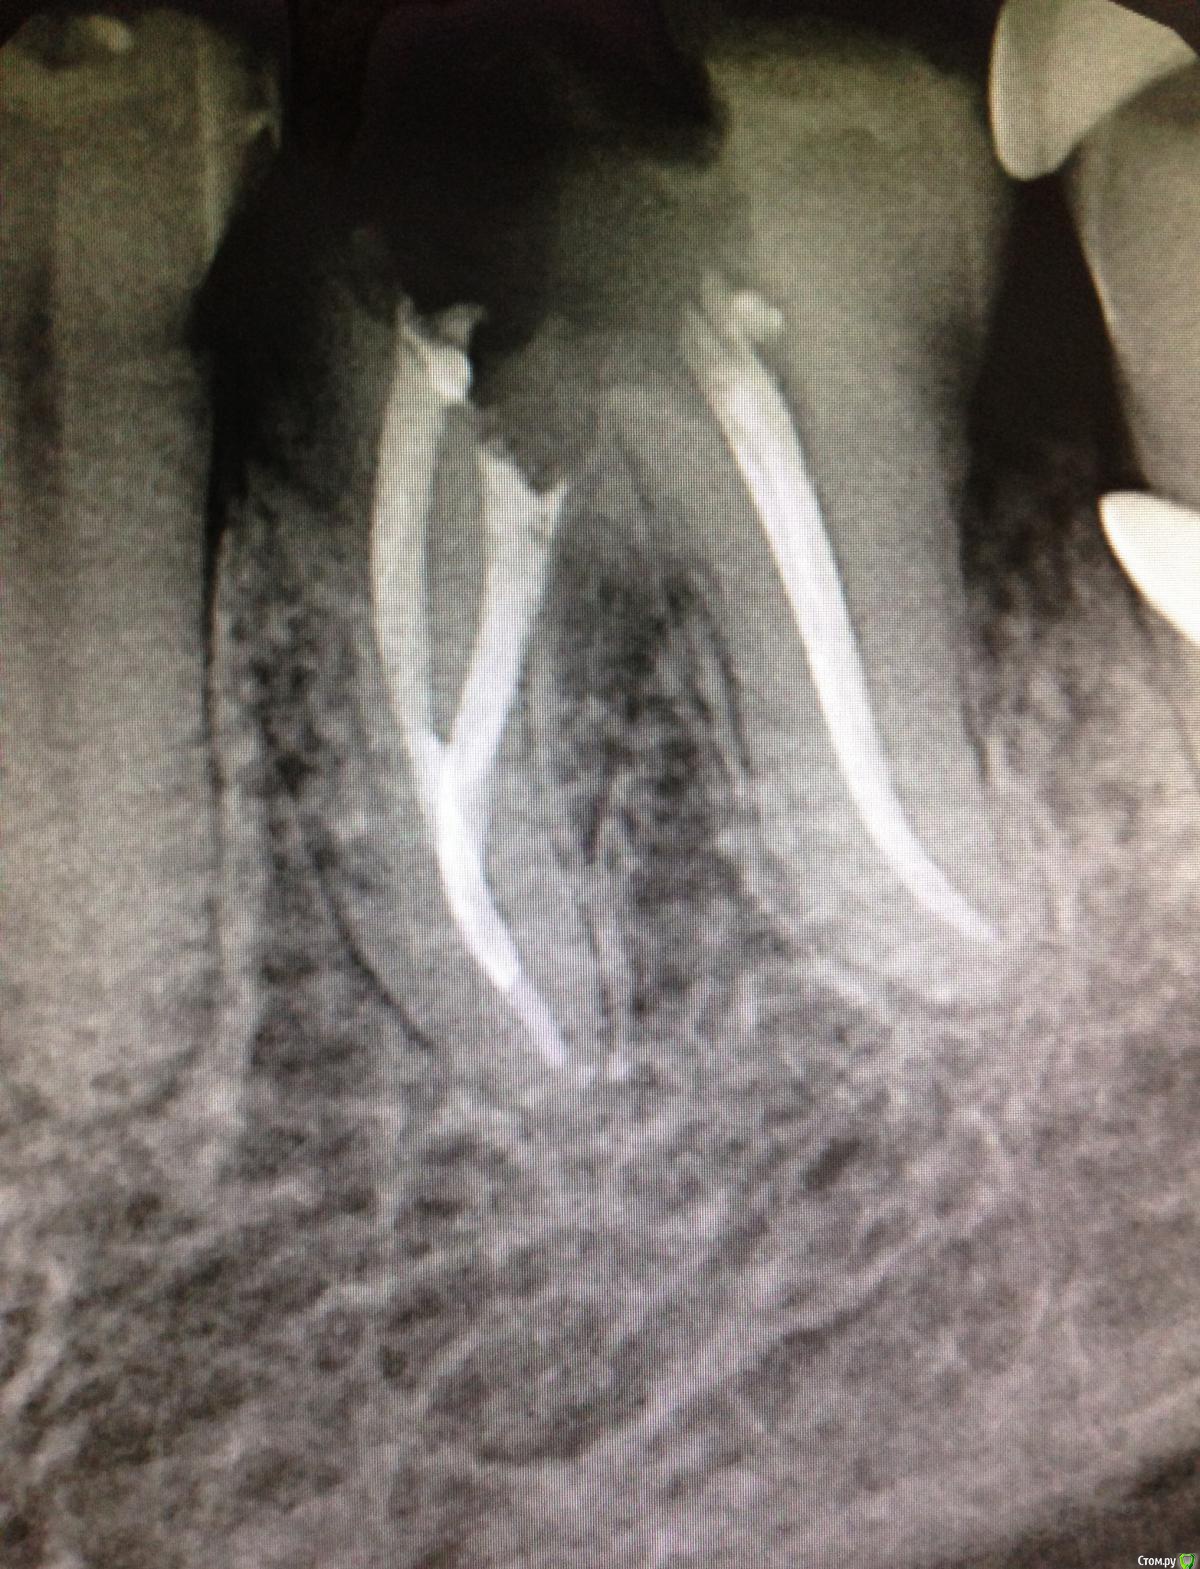

SSTi Опубликовано 9 декабря, 2014 Автор Поделиться Опубликовано 9 декабря, 2014 Чуть обновимся. Пульпитный 36. Медиальные профайлы 35.04. Дистальный 40.04. ОХАП 37. Резорцин старый. Через кальций. 12 хап. 13 пульпит. 60 упор 5 Ссылка на комментарий